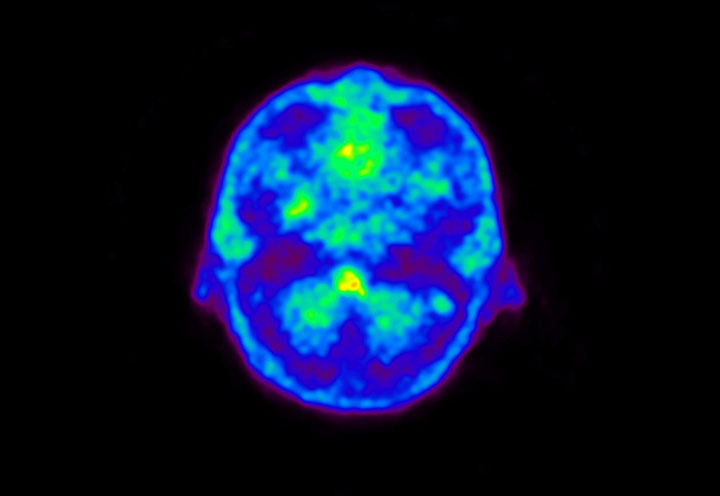

Head / Case5 : Amyloid

Courtesy : Kindai University Hospital

- Imaging protocol

- Injected dose: 4.27 MBq/kg, 18F-Flutemetamol

- Uptake time: 99 minutes

- Scan time: 20 minutes